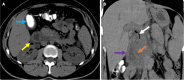

Endoscopic retrograde cholangiopancreatography (ERCP) is a cornerstone procedure for the diagnosis and management of pancreatic and hepatobiliary diseases. Although its diagnostic role has been increasingly supplanted by noninvasive imaging modalities such as magnetic resonance imaging (MRI) and magnetic resonance cholangiopancreatography, the therapeutic applications of ERCP have continued to expand. ERCP is widely used and has a generally favorable safety profile. However, it is important to recognize expected post-procedural imaging findings and serious complications that can arise. The increasing complexity of therapeutic interventions and the growing volume of procedures have led to a higher incidence of complications that often present with overlapping clinical and laboratory features, underscoring the critical role of imaging in differential diagnosis. This review focused on the typical normal ERCP findings and the imaging characteristics of common complications, including pancreatitis, bleeding, ERCP-related infections, perforations, and stent-related complications. Computed tomography (CT) is particularly valuable in timely recognition, management, and surgical decision-making for these complications. Furthermore, MRI offers a radiation-free alternative for managing complications in selected patients. Therefore, radiological modalities, particularly CT and MRI, are critical tools for the rapid diagnosis, management, and surgical decision-making processes for post-ERCP complications.